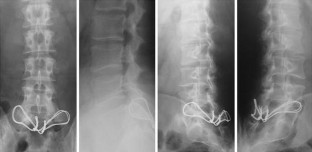

Fig. 1

Fig. 2

Fig. 3

Fig. 4